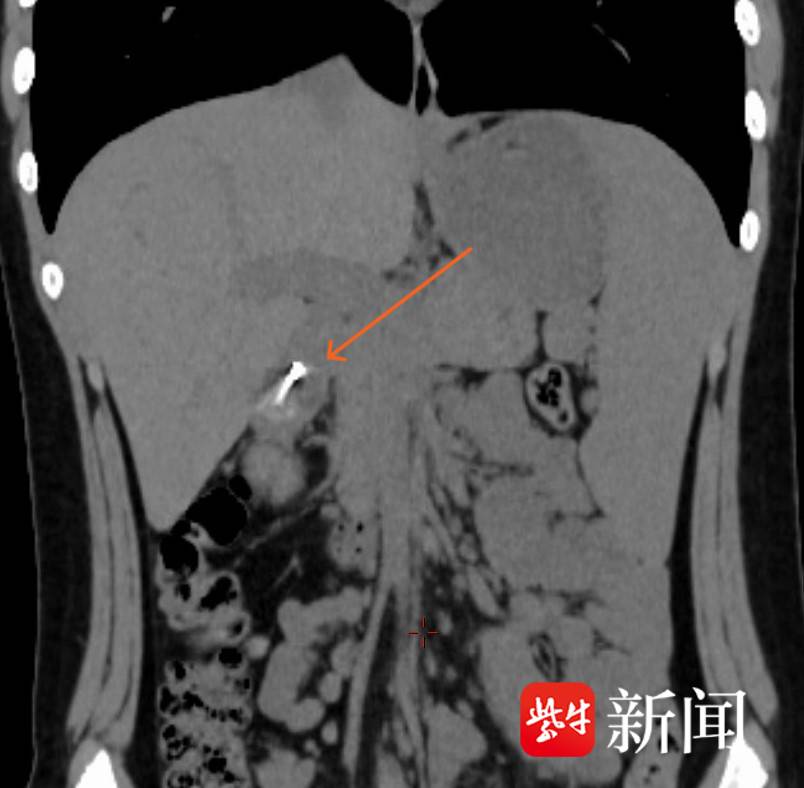

急诊腹部CT显示,胃窦-十二指肠区有长条状高密度致密影,长约19mm。圆规的针尖锐利无比,在孩子稚嫩的体内多停留一秒,就多一分刺伤胃肠道黏膜、引发严重并发症的危险,情况已然万分危急。经院内绿色通道,很快孩子被送至该院内镜中心。